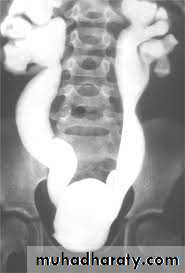

DIAGNOSIS

IVUDIAGNOSIS